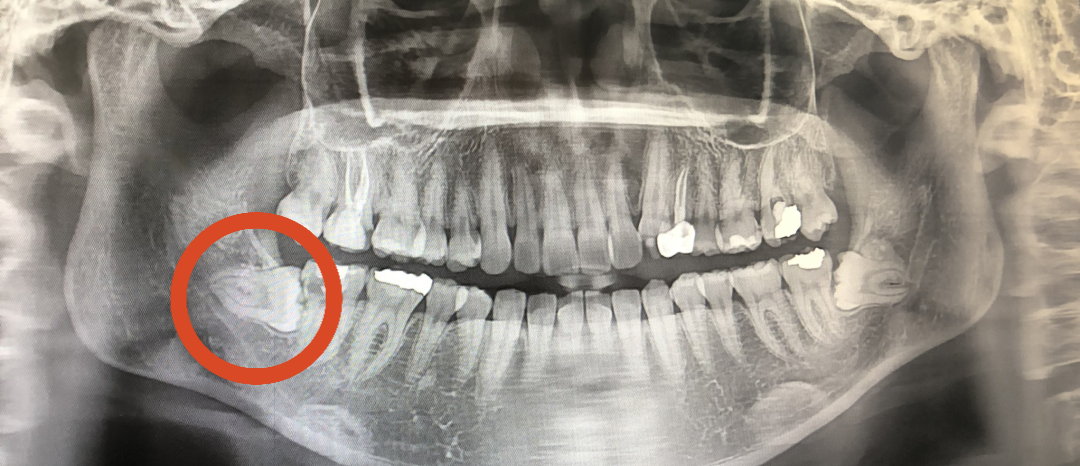

02. 3D-CT를 통해 사랑니의 크기와치아 방향, 깊이, 신경의 위치 확인

02. 3D-CT를 통해 사랑니의 크기와

치아 방향, 깊이, 신경의 위치 확인